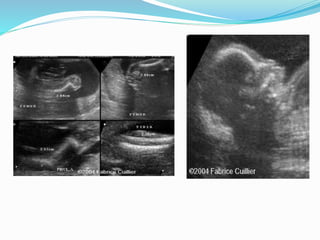

Campomelic Dysplasia

 Features mainly in the lower limb :

 1- Short bowed femur , tibia and Fibula + marked

Talipes

 2- The whole lower limb is bowed inwards hint the

name (Campomelia) derived from a greek word campo

or campto meaning BENT.

 3- marked association with soft tissue involvement

(cardiac, renal and Brain)

Prognosis

 ¾ of the cases die during neonatal period due to

associated pulmonary hypoplasia the prognosis is

mainly dependent on other organ involvement

 Recurrence is around 5%